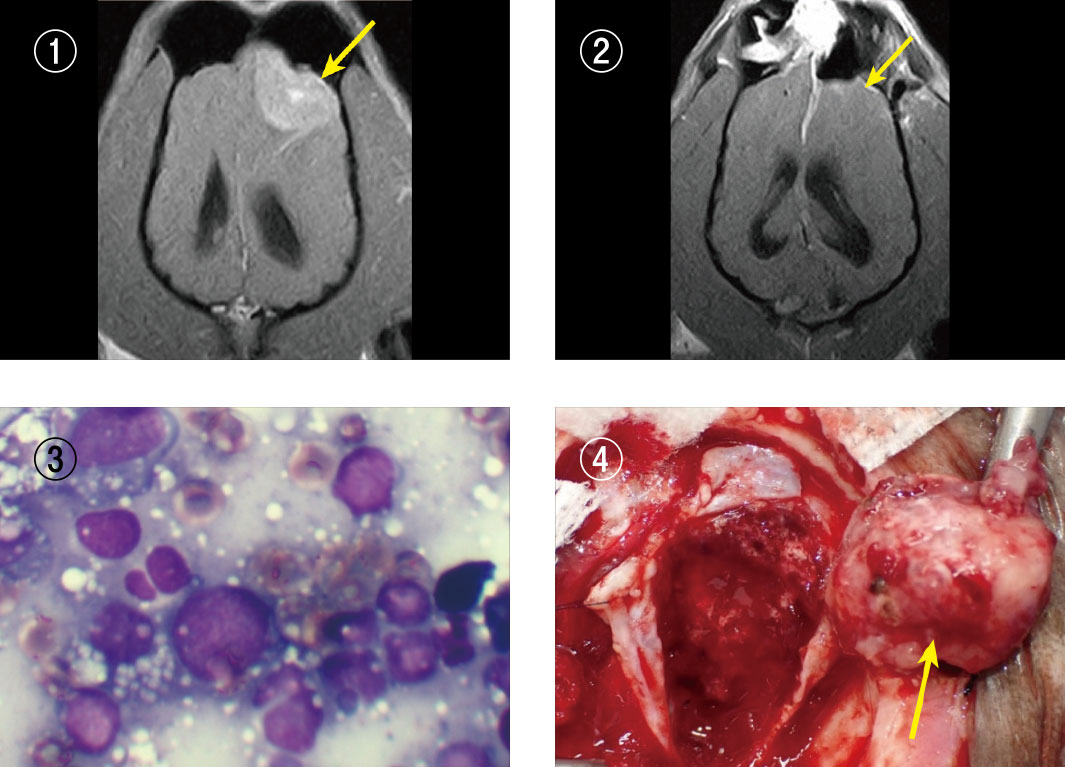

頭蓋内原発組織球性肉腫

10歳のジャックラッセルテリア。発作を起こし意識混濁で来院。MRI検査で脳腫瘍が発見され手術を行いました。肉眼的にすべての腫瘍を取り切りましたが、病理検査で組織球性肉腫と診断され、脳内に腫瘍細胞が残っている可能性が極めて高いことが判明したため、抗がん剤のACNUを3週間ごとに静脈投与しました。長期にわたって腫瘍の再発を抑えることができ、この腫瘍としては異例の490日という長い間頑張ってくれました。

(写真説明)

写真①:手術前のMRI画像。左前頭葉に腫瘍が確認されました。

写真②:手術後のMRI画像。腫瘍は摘出され、画像上消失しました。

写真③:手術中の細胞診。悪性度の高い細胞が多数確認されました。

写真④:手術写真。大きな腫瘍を摘出しました。